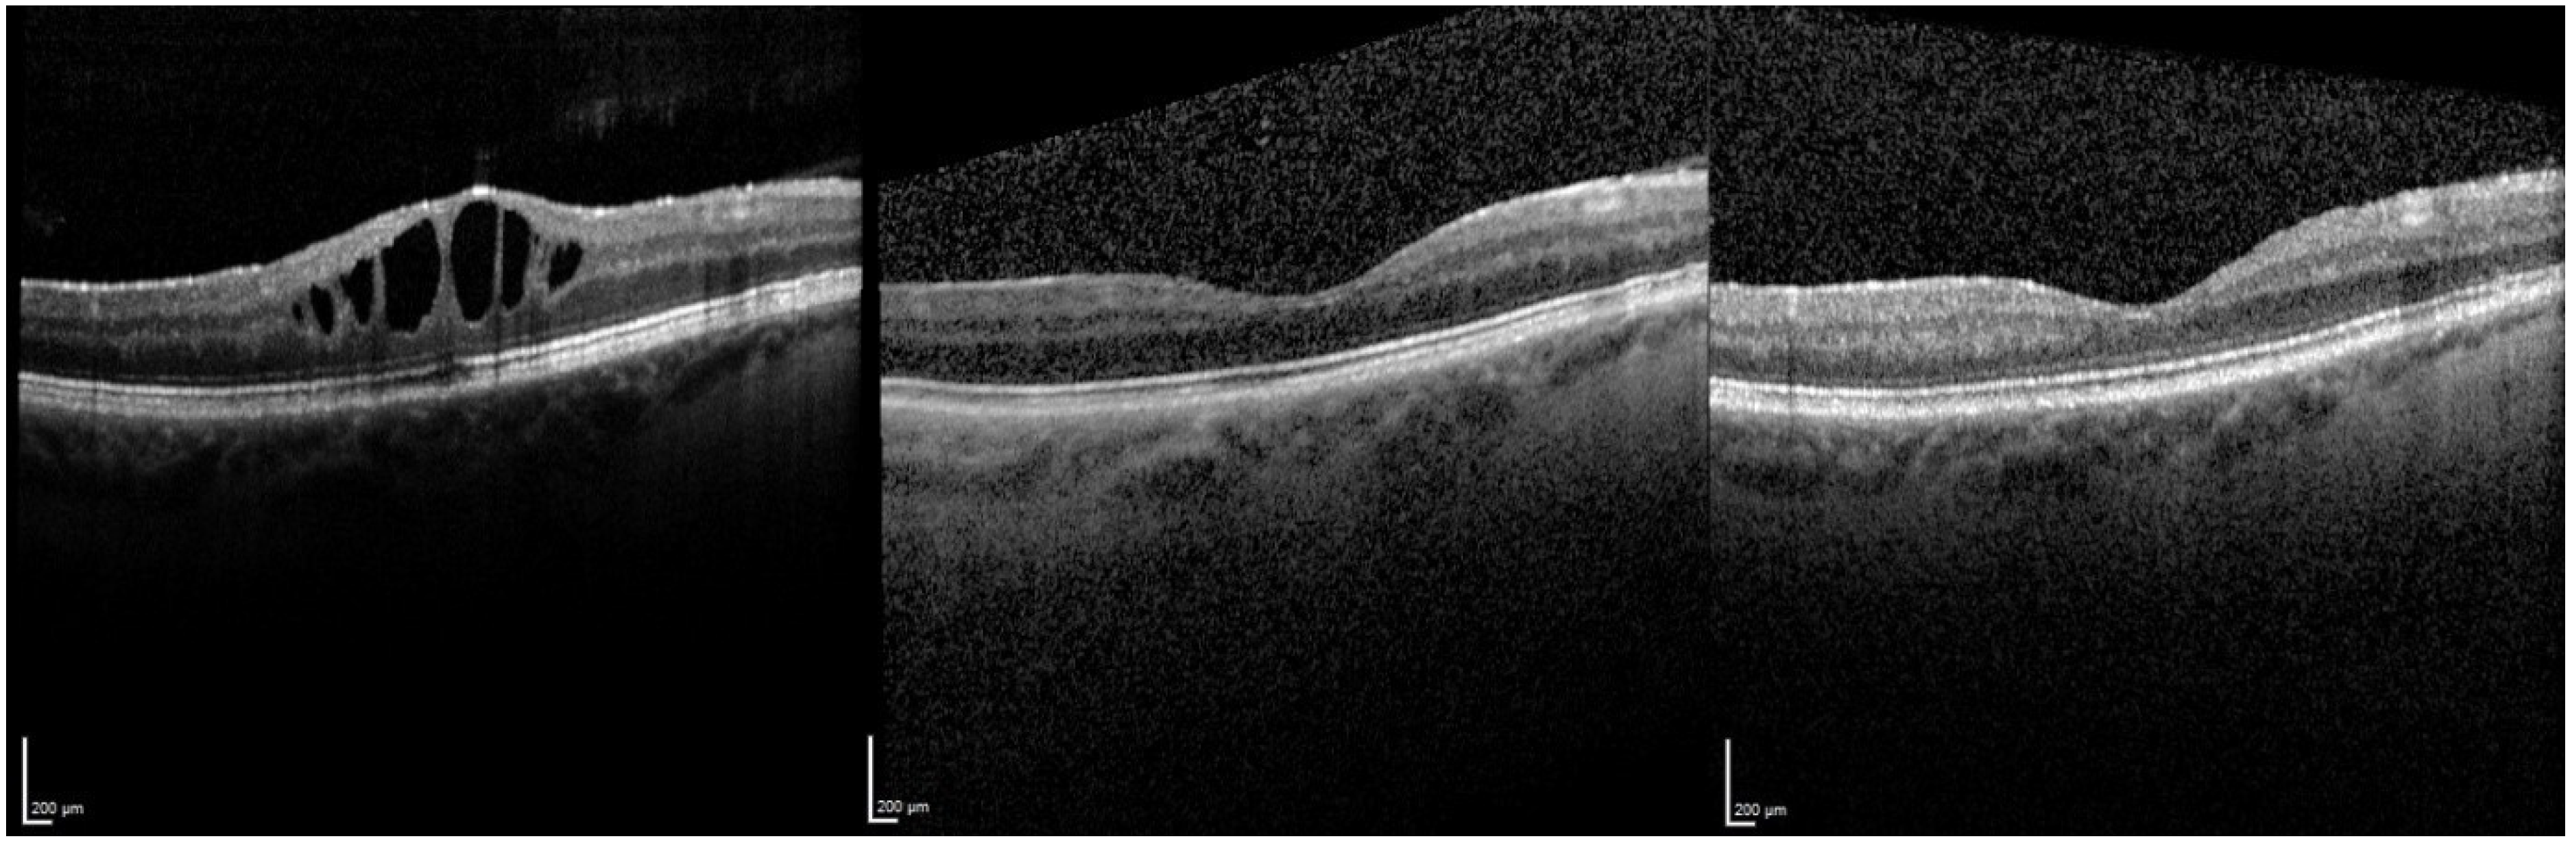

3.1. Central Retinal Thickness (CRT)

3.1.1. Overall Effect of FAc Therapy

3.1.2. Relapse and Retreatment with a FAc Implant

3.1.3. Therapy Failures